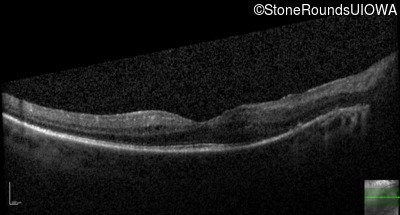

OS

20/40

OCT Stack

20/32 -1